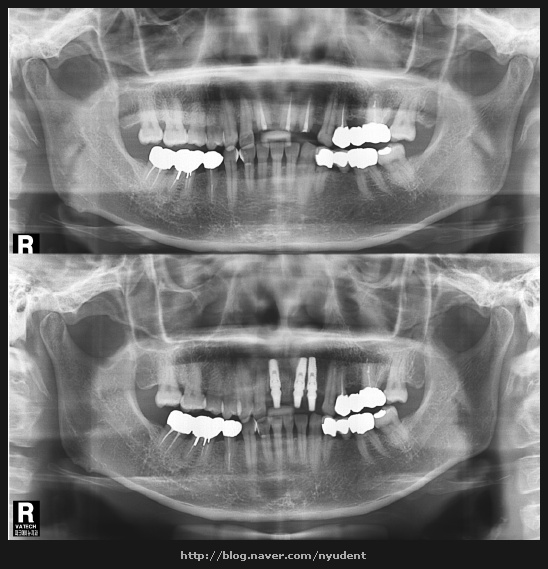

임플란트는 임플란트를 식립하고 그 위에 최종 보철물 (보통 크라운이라고 하죠)이 연결되어 치아가 만들어 집니다

‘따라서 임플란트와 보철을 함께 전공하신 원장님께서 시술하시는 것이 가장 바람직합니다

임플란트와 보철을 둘 다 전공하신 원장님께 임플란트 수술을 받는것이 가장 바람직합니다

파크에비뉴치과는 임플란트를 전공한 대표 원장님께서 직접 임플란트 시술을 해주십니다

임플란트 전문의가 아닌 분이 해주시는 것과는 결과 면에서 많이 다를수 있습니다